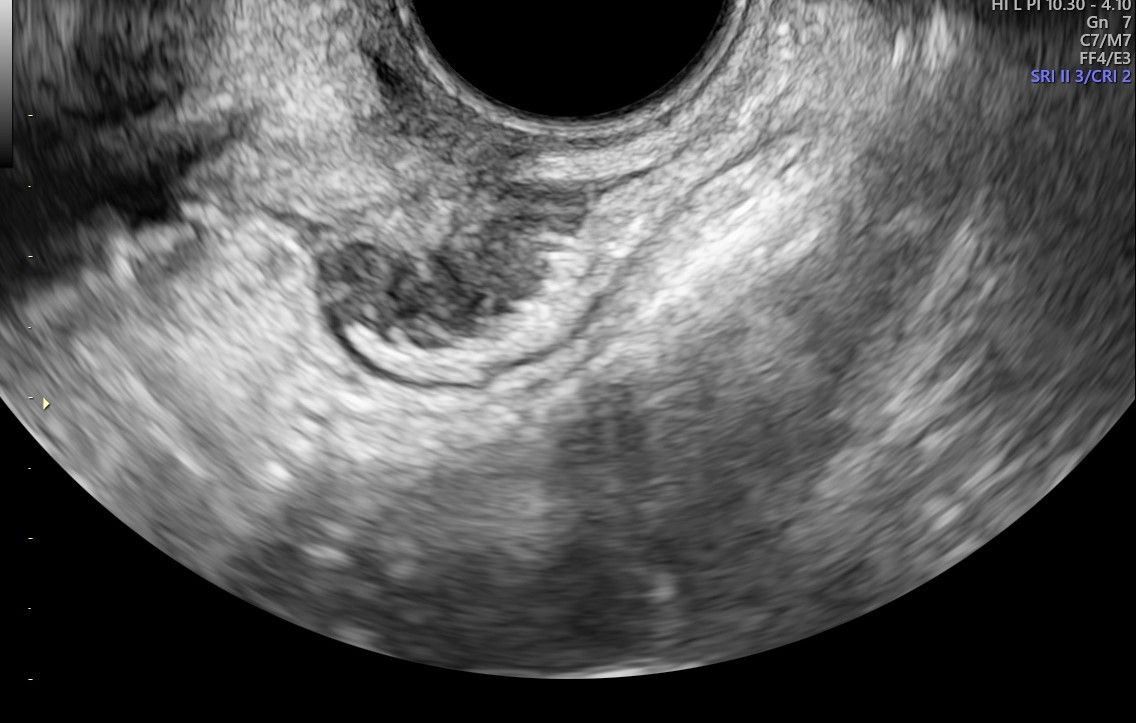

diagnostica ecografica tranvaginale con eco color doppler di I e II livello e transaddominale

Foto e video